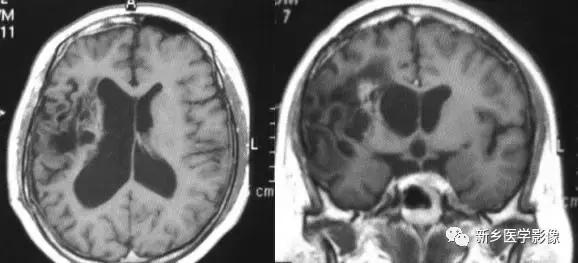

CT和MR均能够很好显示无脑回和巨脑回畸,表现为大脑半球表面几乎呈光滑状,仅可见少数宽阔、粗大、平坦的脑回,脑沟缺如.脑灰质增厚,脑白质变薄,灰白质分界面异常平滑,见不到白质向灰质内伸入的现象。常见透明中隔腔存在.侧脑室扩大,蛛网膜下腔增宽。

(3)无脑回和巨脑回

无脑回和巨脑回是一组因神经元移行异常所致的脑回发育异常。巨脑回也称平滑脑。巨脑回指有部分脑回存在,这些脑回异常增大增宽.脑沟变浅。巨脑回主要位于额、颞部。无脑回上要位于顶、枕部。

临床上,无脑回和巨脑回畸形患儿均表现有小头畸形和轻微的面部异常,完全无脑回畸形常在两岁前死亡.不完全无脑回畸形存活常能长期。